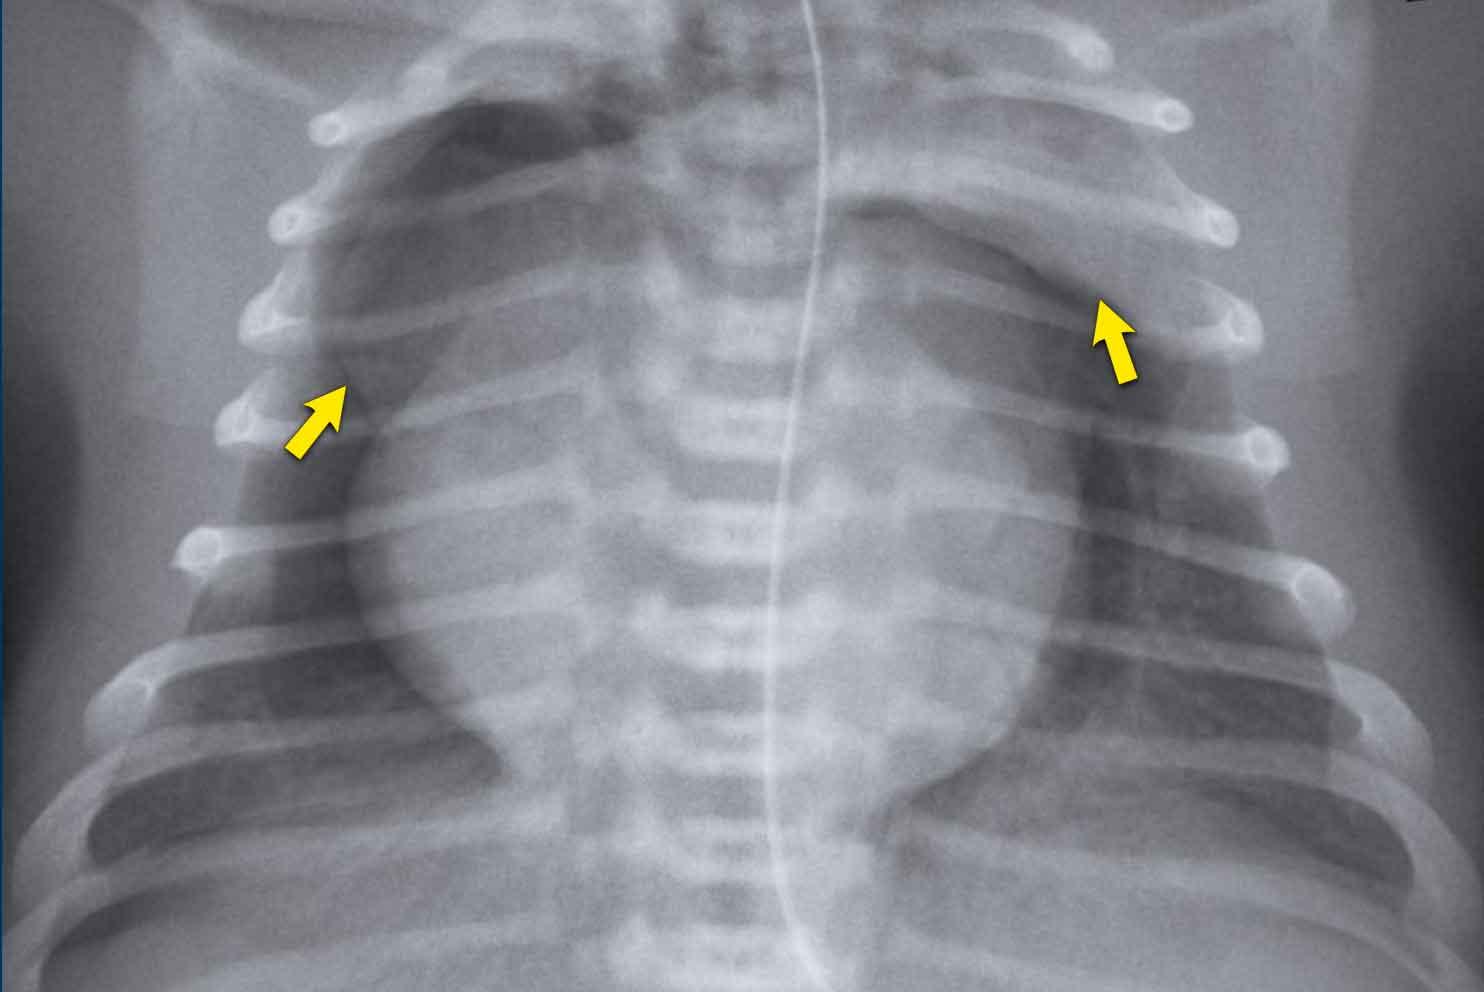

Trẻ sơ sinh, tuổi thai 37+6 tuần, suy hô hấp, được điều trị bằng CPAP sau sinh. Tiền sử mẹ có nhiễm trùng.

First study the image.

What are the findings.

Hình ảnh

Tăng thể tích phổi hai bên với tăng độ mờ không đối xứng của phổi kèm theo đông đặc nhẹ thùy trên phổi phải (mũi tên đen) và thùy dưới phổi trái (mũi tên trắng).

Ứ khí thùy trên phổi trái.

Trẻ này xuất hiện các dấu hiệu nhiễm trùng, cả về lâm sàng lẫn kết quả xét nghiệm.

Các hình ảnh X-quang được quy cho viêm phổi sơ sinh.